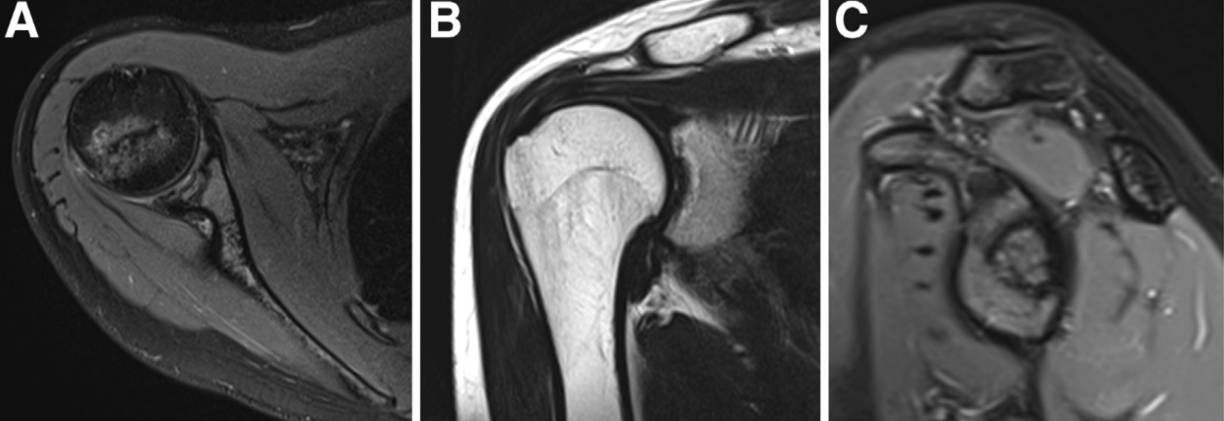

Recent studies have evaluated the progressive joint damage stages (from I to IV) according to the International Cartilage Research Society (ICRS) OCD grading on the basis of magnetic resonance imaging (MRI). (3)

It was demonstrated that, despite the different concave shape of the glenoid, its OCD follows the same progression over the time of the convex weight-bearing articular surfaces and needs, likewise, the same gradespecific management. Patients with IRCS OCD stage I and some with OCD stage II present with a stable shoulder and can undergo conservative treatment. Unstable or advanced glenoid OCD stages, characterized by disruption of the articular cartilage and the presence of separated fragments as loose bodies, require surgical treatment. Moreover, this is indicated when the conservative approaches fail, especially because of long-standing pain and joint range of motion worsening. Proposed surgical treatments include arthroscopic drilling, microfractures, debridement of the unstable osteochondral fragments, and fixation with suture anchor or autogenous osteochondral plugs, platelet-rich plasma, and gellike sodium hyaluronate. (2,4) There is not yet consensus regarding the ideal technique. In this Technical Note, we describe an arthroscopic procedure with a single-layer hyaluronate-based scaffold for the treatment of OCD of the glenoid.